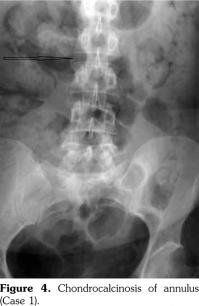

On examination, there was swelling and painful restriction of movement in her right knee. Imaging revealed calcification of cartilage of wrists, knee joints and hip joints although no microscopic confirmation was possible at this stage (Figure 1-4). She was investigated for a possible cause for CC, although investigations to screen for a metabolic cause turned out to be negative with a possibility for hereditary CC.

His hand X-rays showed hook like projections arising from radial aspect of second and third metacarpal heads with scapholunate advanced collapse and indentation of distal radius by the scaphoid bone. It also showed CC of the triangular fibrocartilage (Figure 6).